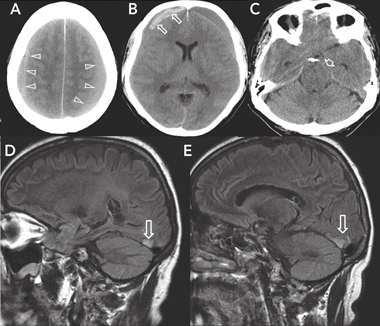

A cerebral computed tomography (CT) scan showed large bilateral frontoparietal subdural haematomas (Box 1, A). The right-sided haematoma had mixed hyperdense and isodense areas suggestive of acute on subacute bleeding, while the left frontal haematoma was isodense. The CT scan also showed marked mass effect (Box 1, B) and early tentorial herniation of the uncus (Box 1, C) without tonsillar descent. There was a delay of 8 hours, including transfer of the patient to a neurosurgery centre, before surgery. The patient’s medical notes showed that before undergoing surgery he had developed bilateral extensor Babinski responses and had a GCS score of 14/15. One hour before the operation, the nursing records indicated “GCS 13/15, patient too drowsy and disoriented to consent [to surgery]”. No further imaging was undertaken and no further notes were made before surgery.

Magnetic resonance imaging (MRI) of the brain and orbits conducted 6 months after the surgery showed chronic infarction involving the inferior tip of both occipital lobes medially, more marked on the right side (Box 1, D and E). There was evidence of residual blood products from the evacuated bilateral subdural haematomas, with no evidence of new bleeding. There was no abnormality of the optic nerves or optic chiasm, and venous drainage on magnetic resonance venography was normal.

1 Initial computed tomography scan of the brain (A–C), and magnetic resonance images 6 months later (D, E)